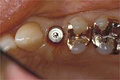

入れ歯が動く人

| 入れ歯は噛みづらかったり、発音発声に不便を感じたりする場合があります。入れ歯をしっかり固定します。 | ![]() |

| インプラントは数本のインプラントを埋入し、そこに入れ歯を固定するため、よく噛むことができます。 |

![]() 下顎にインプラント植立し、安定装置をつけた状態 |